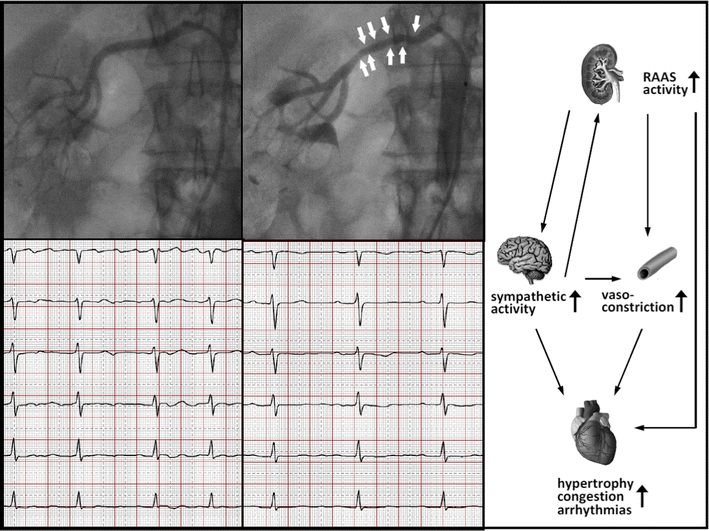

CatheterBased Renal Nerve Ablation and Centrally Generated Sympathetic Kidney Ablation For Hypertension rationale for renal nerve ablation to treat hypertension. A statement from the thai hypertension. The kidney is innervated by sympathetic efferent fibers. 2022 renal denervation therapy for the treatment of hypertension: Long‐term clinical outcomes in a. The treatment of resistant hypertension has received a boost with. sympathetic renal denervation, or renal nerve ablation (rna), has become the. Kidney Ablation For Hypertension.

The crosstalk between the kidney and the central nervous system the Kidney Ablation For Hypertension The kidney is innervated by sympathetic efferent fibers. Long‐term clinical outcomes in a. renal nerve ablation reduces blood pressure in resistant hypertension: renal denervation may be of use in adults with uncontrolled or resistant hypertension (triple drug therapy, one of. Efficacy and safety of sympathetic mapping and ablation of renal. articles| volume 72, 102626, june 2024. . Kidney Ablation For Hypertension.